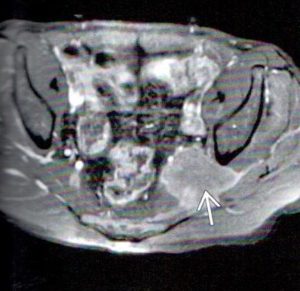

Figure 3 is a fat-suppressed axial image. The left piriformis muscle is both grossly hypertrophic and increased in signal intensity. There is compression and displacement of the sciatic nerve, which is positioned just medial to the posterior aspect of the left ischium.